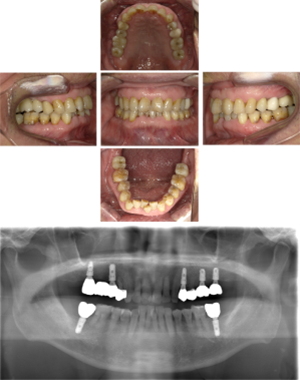

40代 女性 インプラント治療(GBR)

| 年代・性別 | 40代・女性 |

| 主訴 | 硬いものが咬めなくなってきたため、咬めるようになりたい。 |

| 部位 | 右上⑥5④ 右下6 上顎②11② |

| 治療期間 | 約1年2ヶ月 |

| 費用 | ¥2,099,900(税込) |